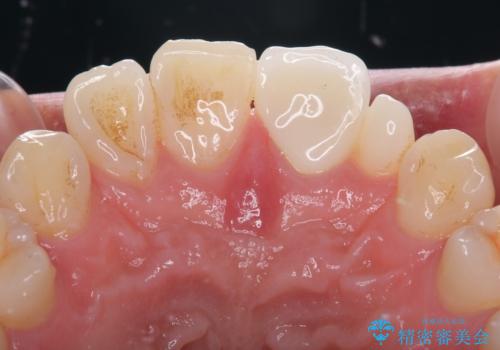

- 隙間を埋めた材料の変色や形を気にして来院された患者様です。

矯正治療などを含めて治療方法を相談した結果、当該歯をオールセラミッククラウンにて補綴治療を行うこととしました。

前歯の単独歯の補綴治療であったので、オーダーメイドタイプをおすすめしましたが、今回は既製タイプにて製作を進めました。

既製タイプでしたが、違和感のない仕上がりとなりました。